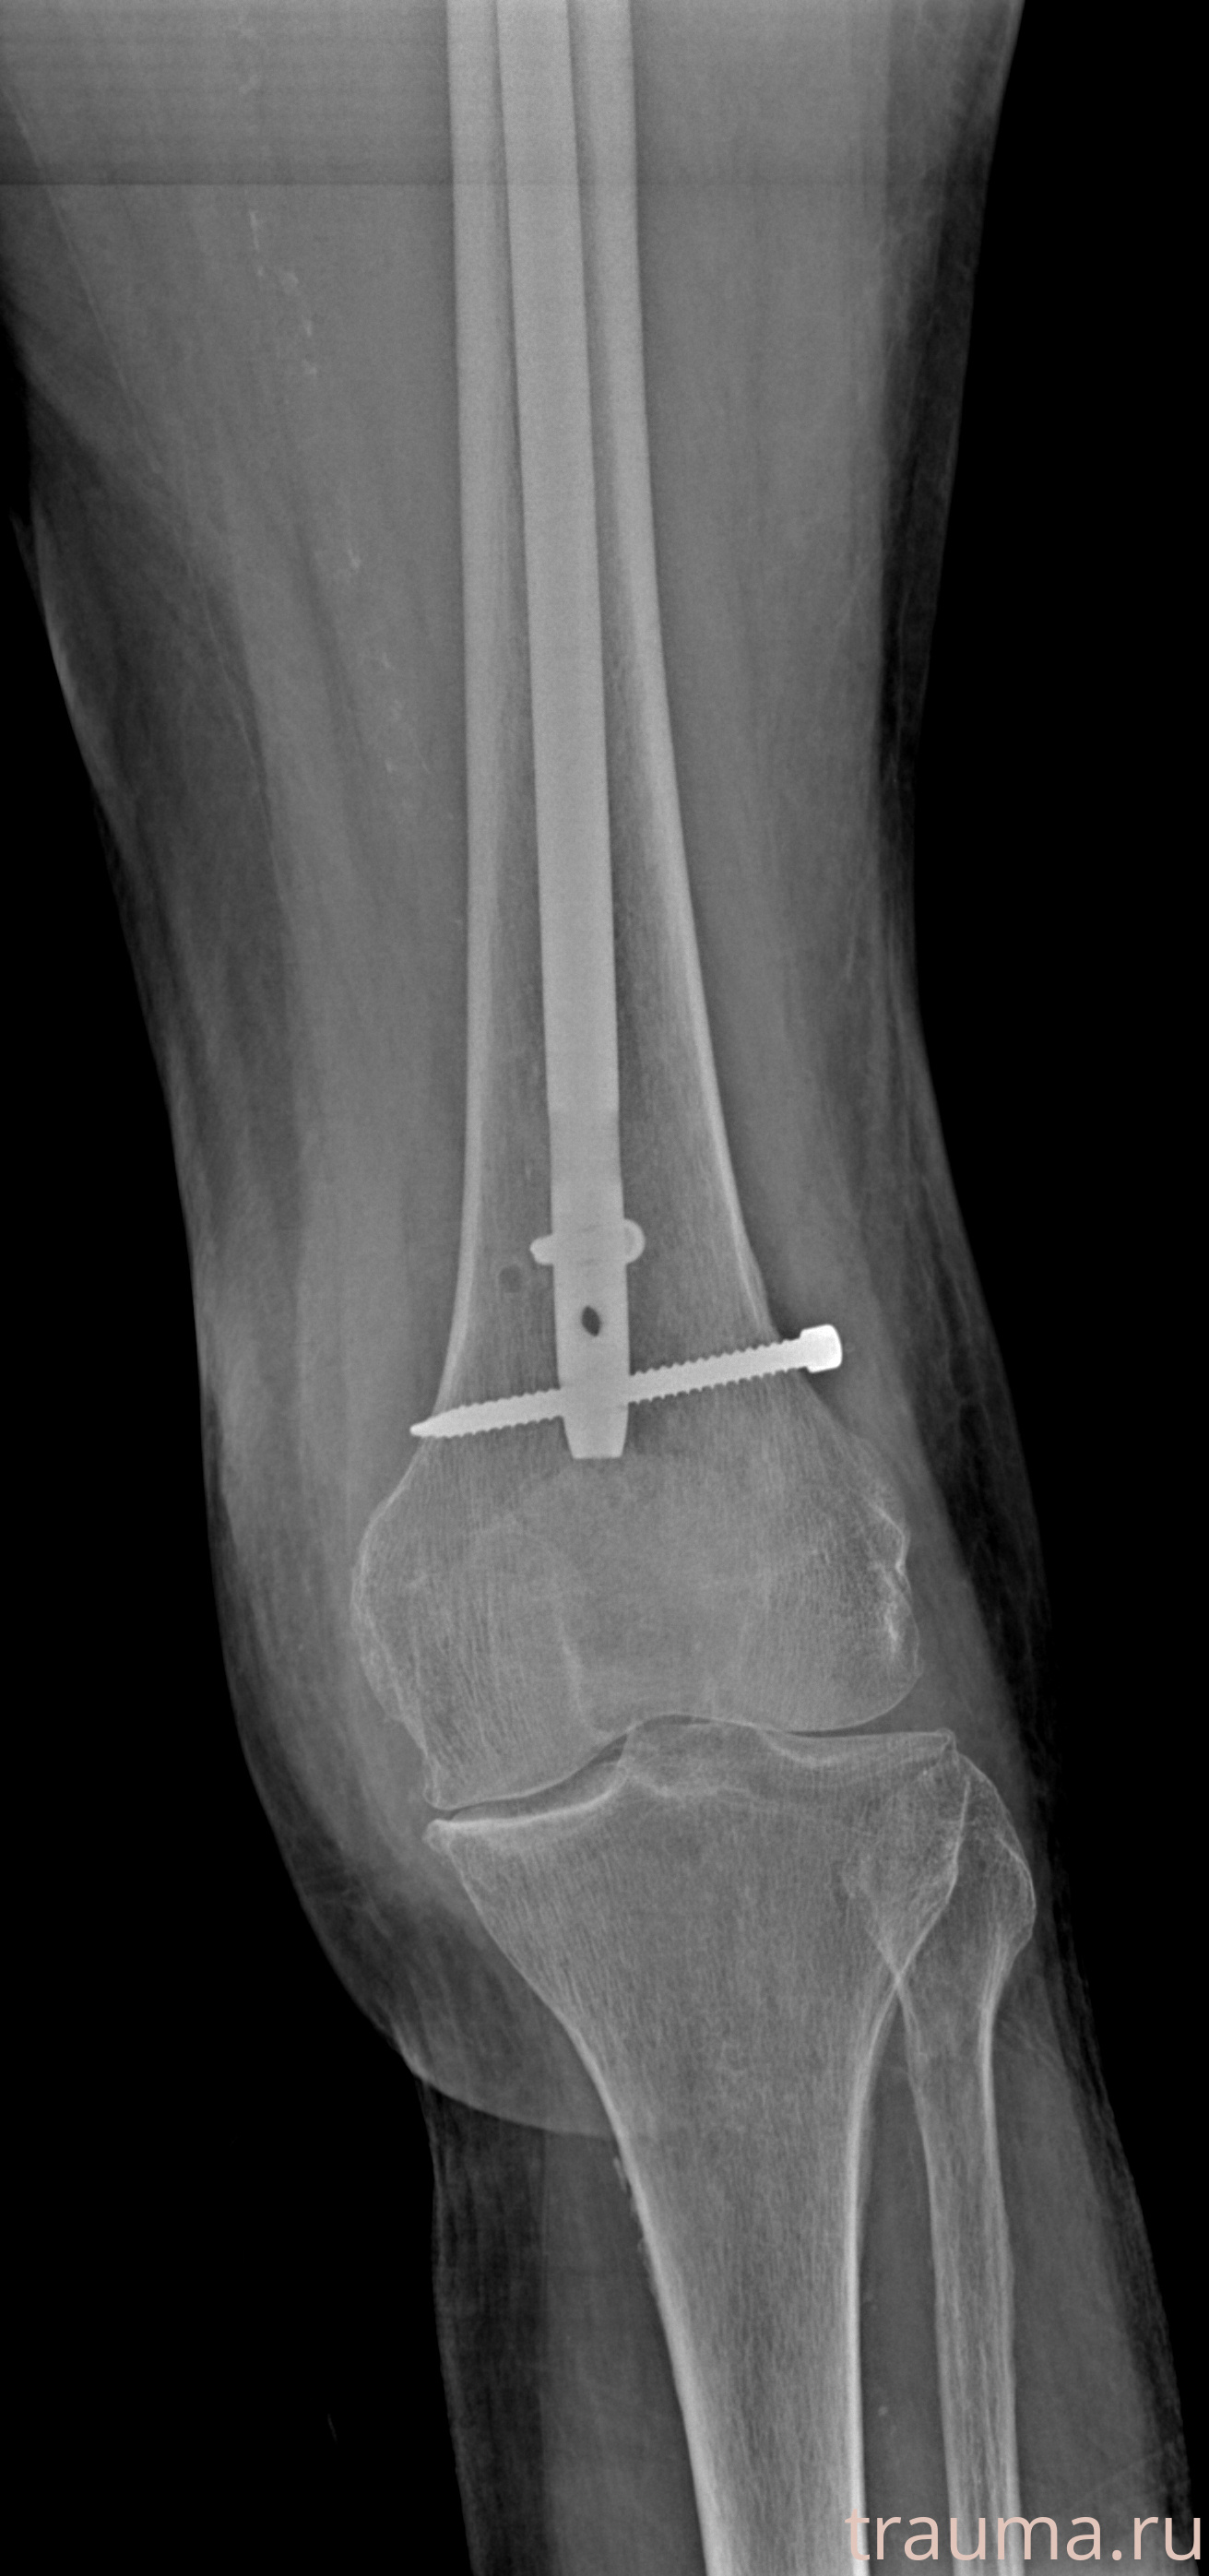

Рентгенограммы

Рентген на дому: по вашему адресу приезжает врач-рентгенолог, травматолог-ортопед с мобильным рентгеновским аппаратом, проводит диагностику травмы или заболевания, делает необходимые рентгенограммы, дает рекомендации по дальнейшему лечению. Получить качественные снимки в домашних условиях возможно благодаря уникальной методике, разработанной МосРентген Центром для института  Склифосовского